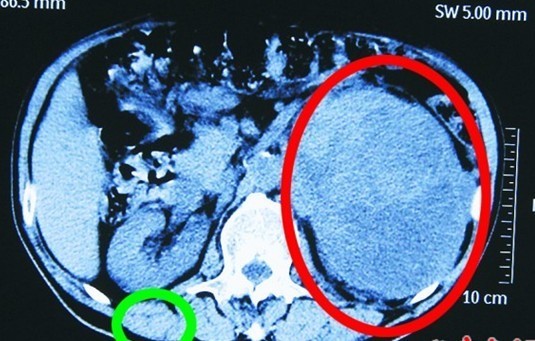

患者王先生的肾脏(图中绿圈处)和巨大肾肿瘤(图中红圈处)。